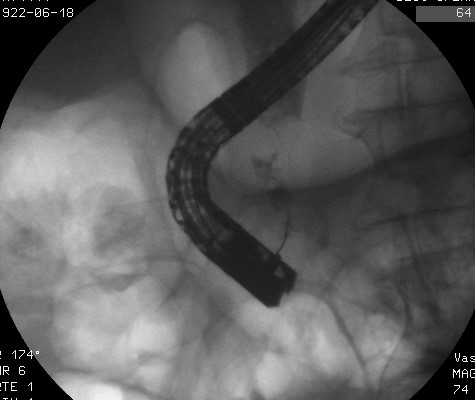

paradormirmejor.org height= »400″ /> cholangiogrtaphie rétrograde: image de sténose irrégulière.

Prothèse biliaire en place